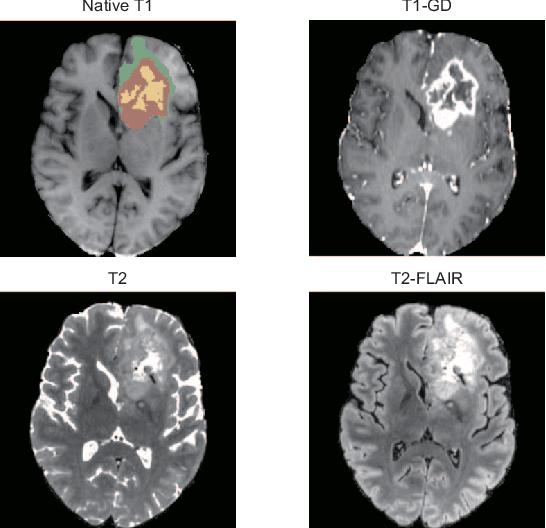

Brain tumor segmentation is essential for the diagnosis and prognosis of patients with gliomas. The brain tumor segmentation challenge has continued to provide a great source of data to develop automatic algorithms to perform the task. This paper describes our contribution to the 2021 competition. We developed our methods based on nn-UNet, the winning entry of last year competition. We experimented with several modifications, including using a larger network, replacing batch normalization with group normalization, and utilizing axial attention in the decoder. Internal 5-fold cross validation as well as online evaluation from the organizers showed the effectiveness of our approach, with minor improvement in quantitative metrics when compared to the baseline. The proposed models won first place in the final ranking on unseen test data. The codes, pretrained weights, and docker image for the winning submission are publicly available at https://github.com/rixez/Brats21_KAIST_MRI_Lab